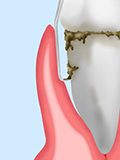

歯周ポケットがさらに深くなり、顎の骨は大きく溶かされています。

歯は支えを失ってグラグラし、膿が出て口臭が強くなります。